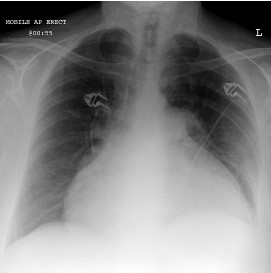

Mulher de 50 anos chega à Emergência com queixa de dispneia e desconforto torácico. Apresenta história de dor torácica intensa, manejada em hospital do interior como infarto do miocárdio sem estratificação invasiva, há uma semana. A paciente apresenta PA 90/40mmHg, FC 120mmHg, turgência venosa central e mínimos estertores crepitantes em bases; está fria e com sensório deprimido. RX de tórax (Fig. 1) e ECG (Fig. 2) da chegada estão representados abaixo.

Fig. 1

Frente a esse quadro, qual seria a melhor conduta?